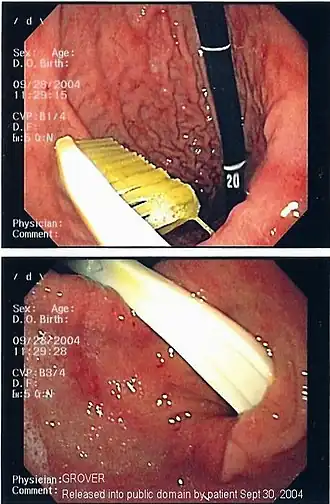

![]() Imagen endoscópica de un cuerpo extraño gástrico (cepillo de dientes) | ||

La presencia del cuerpo extraño se reconoce, de ordinario, a través de la exploración física, de un estudio de imagen o de una exploración endoscópica. Los estudios radiológicos sirven para visualizar y localizar los cuerpos extraños metálicos y radiopacos.

En general, se precisa su extracción sin demora. En caso de que el cuerpo extraño contenga mercurio o plomo, debe de ser extraído lo más pronto posible para prevenir el envenenamiento por mercurio. Las pilas alcalinas de botón contienen un 45% de hidróxido potásico y pueden perforar el tubo digestivo, por lo que tienen que ser extraídas urgentemente.